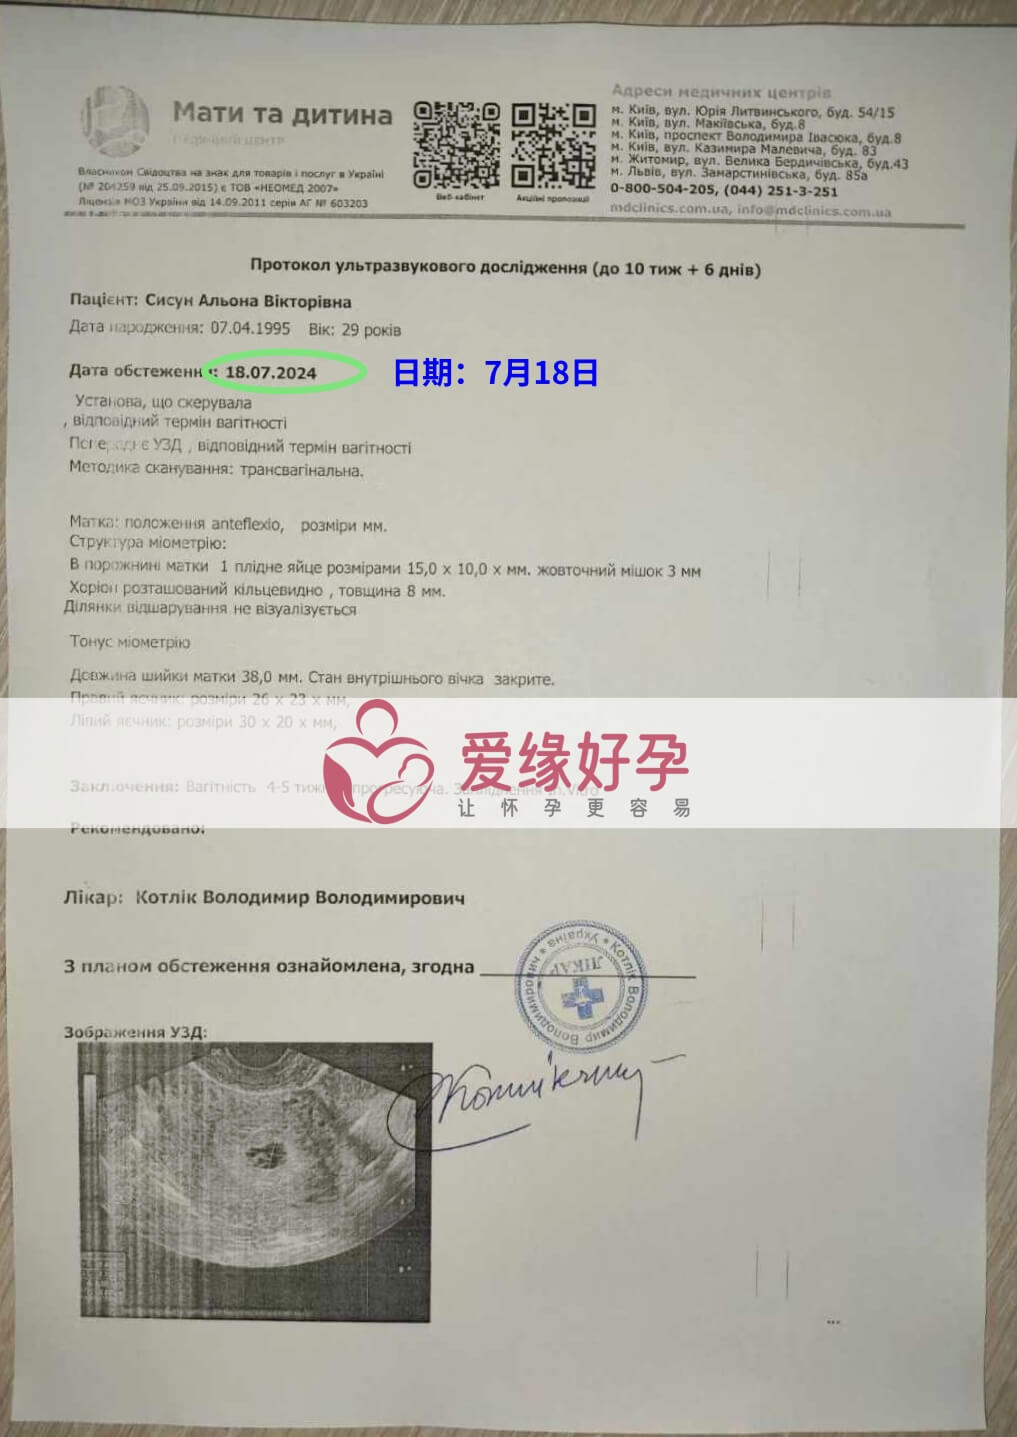

爱缘好孕乌克兰代孕代母孕B超产检顺利通过

发表日期:2024-07-18

乌克兰代孕代母妈妈第一次B超检查确认宝贝发育良好!